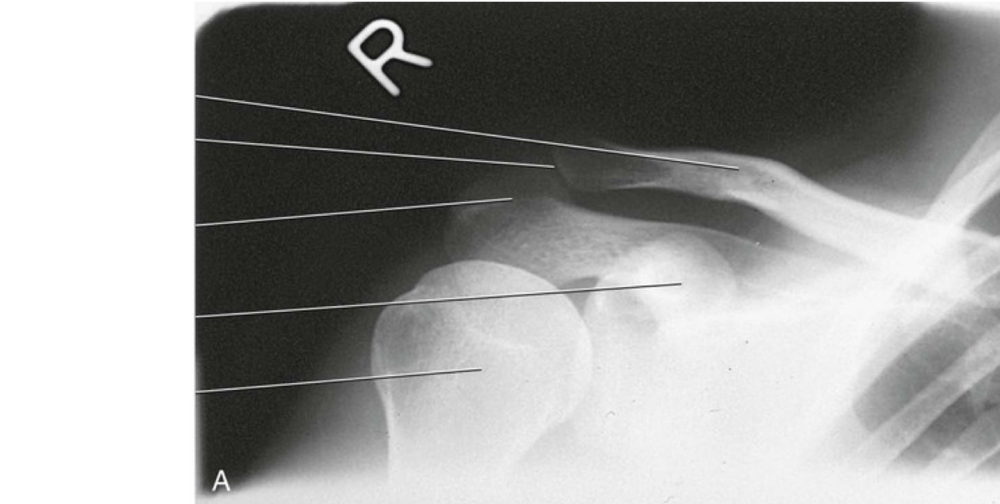

Question 4

Question

Label the image

Image:

2abc4b88-3a7c-4d40-b5a5-c9796dacde75 (image/png)

Answer

greater tubercle

Question 5

2a7f2f74-1bbf-4ace-aca9-e4499490018d (image/png)

lesser tubercle